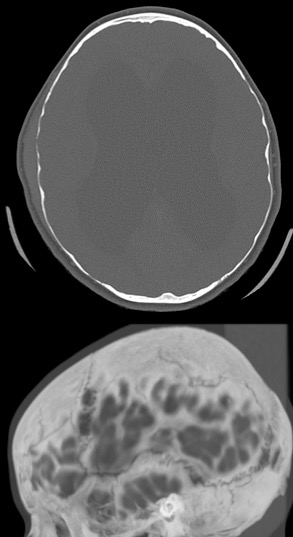

le scanner

l’étude du crâne montre une disjonction des sutures, parfois des lacunes ou un amincissement de la voûte (image ci-contre).

l’IRM

plus difficile à être en oeuvre car plus longue et nécessitant souvent une sédation, c’est elle qui étudie au mieux le tissu cérébral, pour donner des indications sur la cause de l’hydrocéphalie (traces de saignement en période périnatale) et son retentissement et son pronostic (analyse des leucopathies périventriculaires). elle permet également d’étudier le flux du LCS, en pré et en post-opératoire, ce qui oriente la décision chirurgicale.

l’imagerie de référence

du fait du drainage, le patient valvé a le plus souvent des ventricules de

taille inférieure à la normale, de plus, son encéphale est rigide (très peu compliant) ; lors d’une obstruction de valve, les ventricules se dilateront donc peu pour une pression qui peut être très élevée.

inversement, les ventricules peuvent rester larges sans être sous pression.

pour éviter les retards d’intervention ou les interventions intempestives, il est donc indispensable de disposer d’une imagerie de référence (scanner ou IRM).